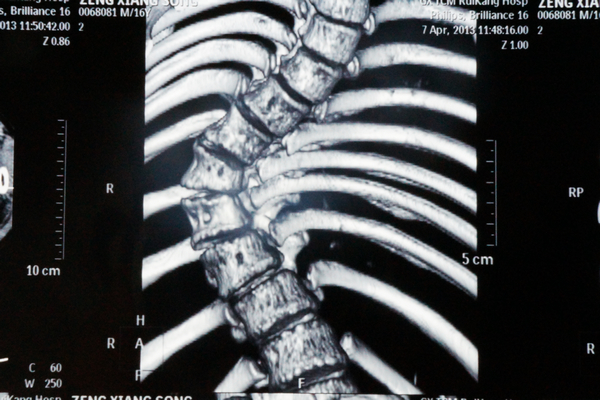

我院骨脊柱二区的医生给小松做了详细的身体检查,发现他的胸5-腰1椎体节段明显向右侧侧弯,呈小“S”形状,胸5-腰1棘突及棘突两旁无明显压痛及叩击痛,右侧竖脊肌肌张力紧张,左侧正常,站立姿势时测量左侧肩比右侧肩高约2cm。同时进行并足前屈弯腰试验时,发现小松的右侧肩胛骨明显高于左侧,出现“剃刀背”畸形,脊柱左右侧弯柔软性差,Cobb角65° ,胸腰椎MRI平扫检查确诊:脊椎侧弯畸形。

小松术前的X光片2